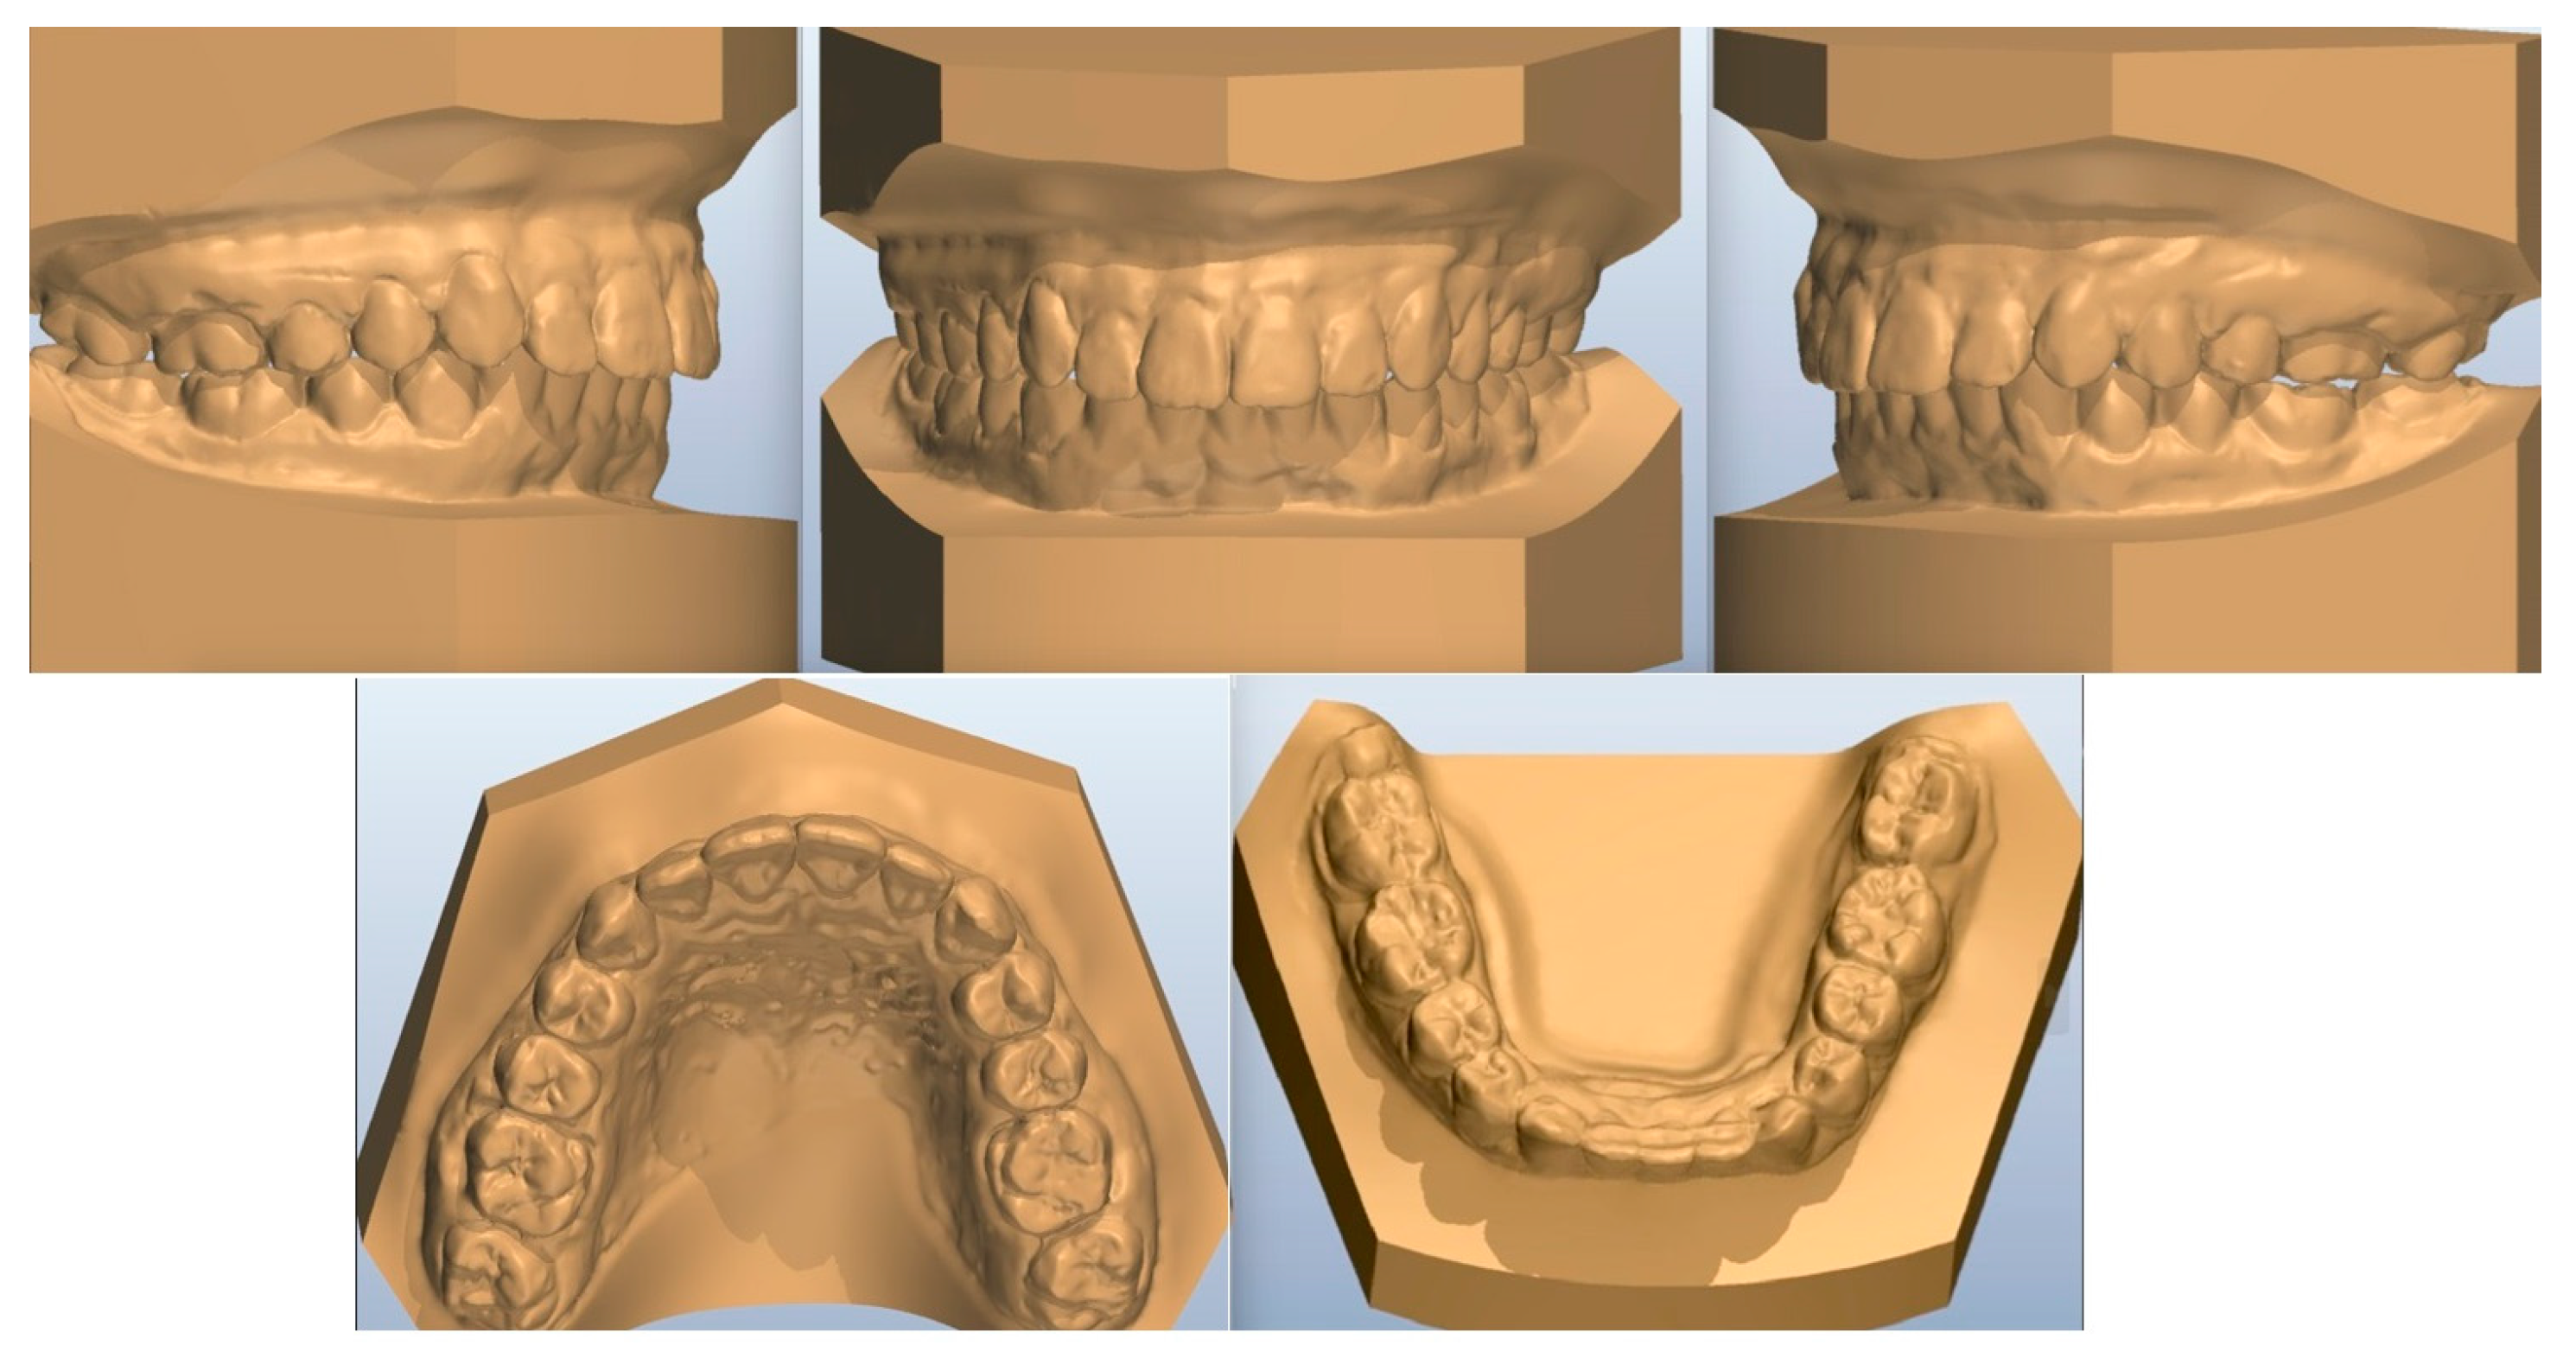

When permanent upper and lower premolars erupted after several months (Figure 3), orthodontic treatment started by placing fixed appliances (0.22 slot edgewise appliance). Digital models, acquired some months later, are presented in Figure 4). Aesthetic pontics (33, 43) with brackets on them were adjusted on the orthodontic wire for social reasons (Figure 5).

Figure 4. Digital models of the patient a few months after fixed appliances were fitted.